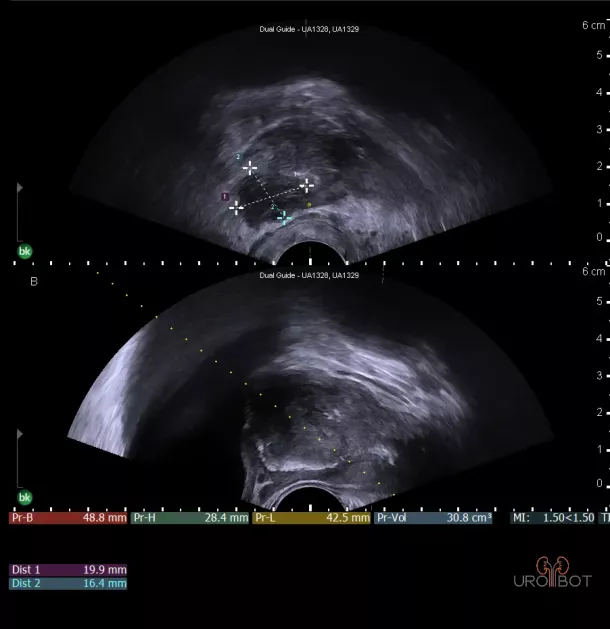

Prostata: Tumorbefund

Auf diesem Bild erkennt man die Prostata in zwei Ebenen mit Hilfe einer in den Enddarm eingeführten Ultraschallsonde.

Der ausgemessene Bereich, etwas dunkler dargestellt, entspricht einem größeren Tumorbefund in der Prostata.

Prostata: Tumorbefund

Auf diesem Bild erkennt man die Prostata in zwei Ebenen mit Hilfe einer in den Enddarm eingeführten Ultraschallsonde.

Der ausgemessene Bereich, etwas dunkler dargestellt, entspricht einem größeren Tumorbefund in der Prostata.